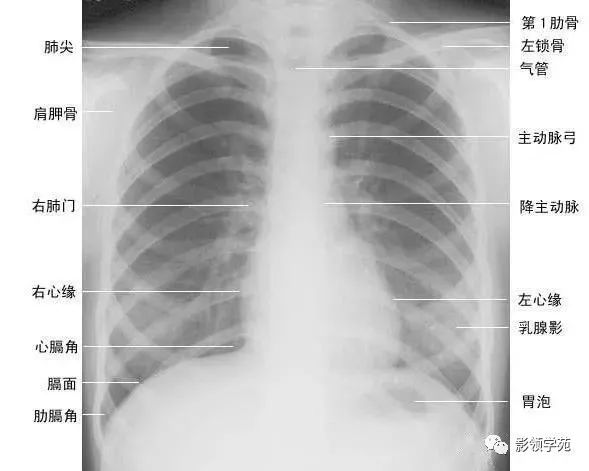

两肺含有空气,因而可与周围组织及器官形成鲜明的自然对比,胸部x线平片为诊断提供了极为有利的条件。由于胸部x线影像是胸腔内、外各种组织和器官重叠的复合影像,同时常常存在解剖变异等因素,因此掌握正常x线解剖是识别和分析胸部病变的基础。

(一)肺野

纵隔两旁含气的肺在胸片上所显示的透明区域称肺野,其透明度随呼吸而改变,深吸气时肺内含气量增多,透明度增高,呼气时则相反。

为便于指明病变的部位,通常人为地将一侧肺野纵向分为三等分,即内、中、外带。又分别在两侧第2、4肋骨前端下缘划一水平线,将肺野横向分为上、中、下三个肺野。一般将第1肋圈外缘以内部分称为肺尖区,将锁骨以下至第2肋圈外缘以内部分称为锁骨下区,将最下肺靠近膈面的部分称为肺基底部(如上图)。

(六)肺门 x线肺门指肺动脉、肺叶动脉、肺段动脉、伴行支气管以及肺静脉构成。

1、正位肺门影后前位胸片上,肺门位于两肺中野内带第2~4前肋间处,通常左侧肺门比右侧高1~2cm,两肺门的大小和密度大致相等。

(1)右肺门可分为上、下两部。上部约占113,由上肺静脉、上肺动脉及下肺动脉后回归支构成。上肺静脉下后干构成右上肺门的外缘;右肺门下部 约占213,由右下肺动脉干构成,其正常宽度不超过15mm,沿中间段支气管外缘平行向外下走行。右肺门上、下部相交形成一钝的夹角,称肺门角,正常该角顶清晰。

(2)左肺门亦分为上、下两部。上部由左肺动脉及其分支、左上叶支气管和左上肺静脉及其分支构成;下部由左下肺动脉及其分支构成,常被心影所遮盖(如下图)。

2、侧位肺门 侧位胸片上,两饲肺门阴影大部分重叠,若以侧位气管轴线为界,右肺门略信其前下,左肺门大部分在其后上。侧位肺门影前缘为右上肺静脉干形成的椭圆形阴影,前后径为2cm左右;中间纵行透亮区为气管及气管分叉,其内圆形透亮影表示支气管开口,右侧在上,左侧居下;后上缘为左肺动脉弓,下缘由两下肺动脉构成下行的树枝状影。因此,侧位肺门影似一尾巴拖长的“逗号”(如上右图):

(七)肺纹理

肺纹理为自肺门向肺野呈放射状分布的树枝状阴影,它主要是肺动脉的投影,肺静脉、支气管和淋巴管也参与形成。平片可显示肺纹理的多少,粗细.分布,有无扭曲、变形与移位等。肺纹理由肺门向外围延伸,逐渐变细,至肺野外带渐细小而稀少,距侧胸壁内缘约1cm范围内的肺野基本无肺纹理可见(图下图)。